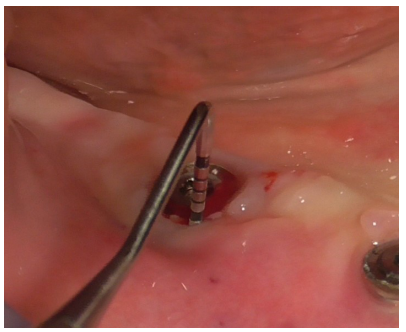

Implant decontamination commenced with an ultrasonic tip (Figure 17) and continued with the diamond ball insert (ES015T) of the Ultrasonic Device (Figure 18).

Figure 17

Figure 18

Additional decontamination was performed with the previously used diamond ball insert for the Ultrasonic Device (Figure 22).

Figure 22